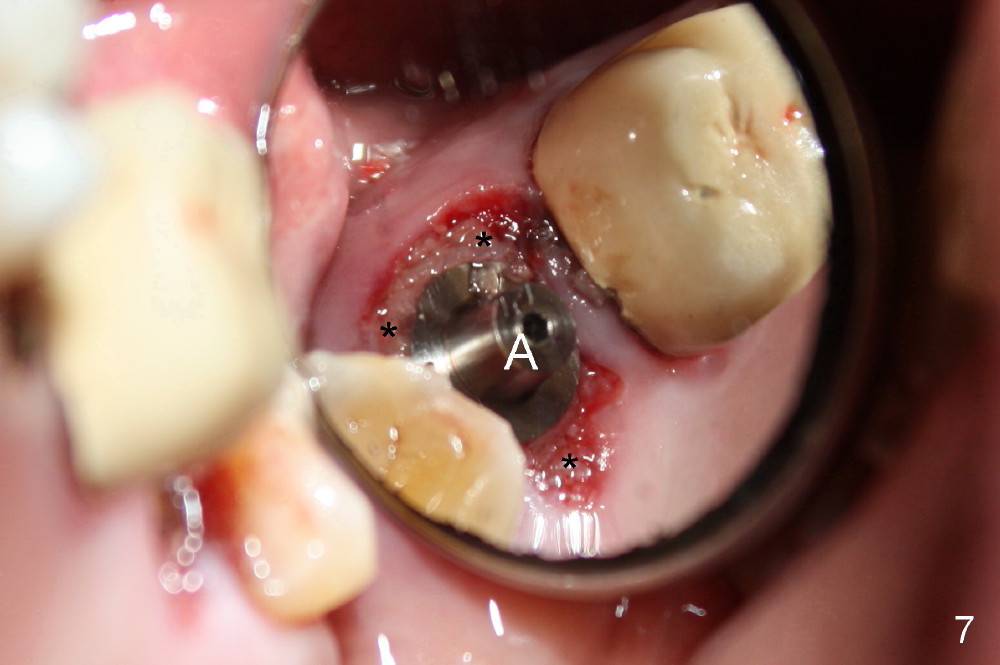

A 66-year-old lady requests restoring a broken tooth (Fig.1). Osteotomy is initiated in a thin septum (Fig.2 (occlusal mirror view) S) by sectioning, drilling and tapping (Fig.3 T). When 7x17 mm tap is removed, the osteotomy is found to form basically in the middle of socket (Fig.4 O). The apical portion of three sockets (Fig.5: MB, P and DB (not labeled) is packed with mixture of autogenous bone and allograft. When a 7x14 mm implant is placed, there are buccal and lingual gaps (Fig.6 *). The latter are bone grafted again (Fig.8 *) and require a coverage. After placement of a 4x3 mm abutment (Fig.7,8 A), an immediate provisional is fabricated (Fig.9 tissue surface view) to cover the remaining sockets (Fig.10 (occlusal mirror view), 11 (buccal view)). The provisional is infra-occlusal, i.e., load-free (Fig.11). The buccal and lingual aspects of the socket are covered by fresh epithelium 8 days postop (Fig.12 <). The implant appears to have osteointegrated 4 months postop (Fig.13). The tooth #16 appears to have shifted mesially. It is difficult to prepare for #15 crown. Luckily the patient agrees to have it extracted because of persistent sensitivity after MO composite. The definitive crown at the site of #15 is cemented 6 months postop (Fig.14).